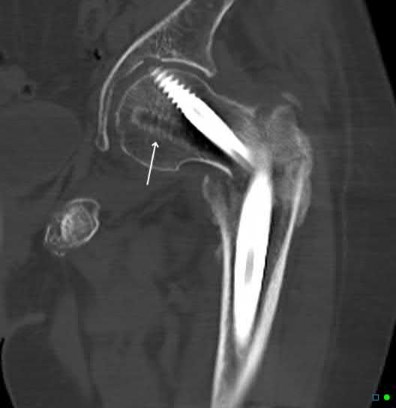

A 12-year-old obese boy presents with vague left thigh and knee pain. He is diagnosed with a Slipped Capital Femoral Epiphysis (SCFE) as seen in similar clinical scenarios.

During percutaneous in-situ fixation, unrecognized penetration of the guide wire into the hip joint occurs. What is the most likely specific complication resulting from this technical error?

Chondrolysis is a severe complication of SCFE characterized by rapid destruction of the articular cartilage. While it can occur idiopathically, its most established iatrogenic cause is unrecognized intra-articular hardware penetration. The 'approach-withdraw' fluoroscopic technique is required during pinning to assure pins are entirely intraosseous. Avascular necrosis (AVN) is usually due to damage to the epiphyseal blood supply (retinacular vessels) secondary to the initial displacement, forceful closed reduction, or posterosuperior pin placement.